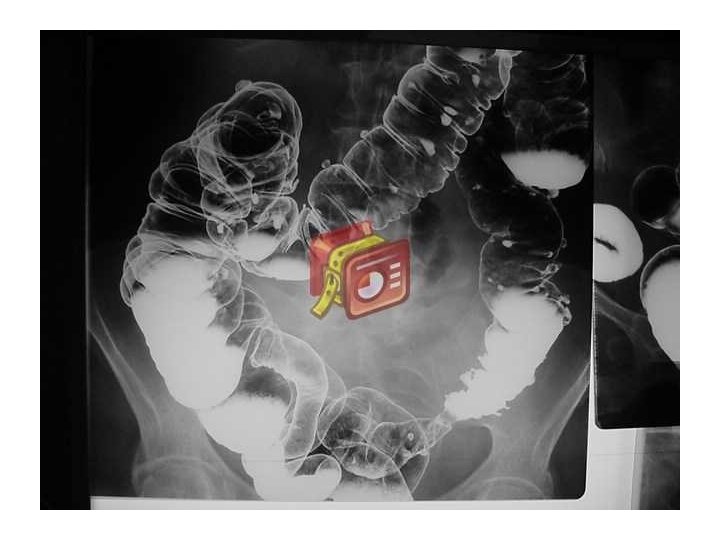

ENFERMEDAD DIVERTICULAR DE COLON • Divertículo: • Protrusión sacular de la mucosa a través de la pared muscular del colon • La protrusión ocurre en las áreas débiles de la pared intestinal donde pueden penetrar los vasos sanguíneos • Habitualmente 5– 10 mm de tamaño • Los divertículos son realmente pseudodivertículos (falsos divertículos), ya que contienen sólo mucosa y submucosa cubiertas de serosa

Enfermedad diverticular • Diverticulosis – presencia de divertículos dentro del colon • Diverticulitis – inflamación de un divertículo • Sangrado diverticular Tipos de enfermedad diverticular • Simple: 75% no tienen complicacionesli> • Complicada: 25% presentan abscesos, fístulas, obstrucción, peritonitis, sepsis

• Distribución – Compromiso sigmoideo – Sólo sigmoideo – Todo el colon – Próximo al sigmoides 95% 65% 7% 4% • Historia Natural – Asintomática – Evoluciona a diverticulitis – Se asocia a sangrado 70% 15– 25% 5– 15%

Divertículos de colon